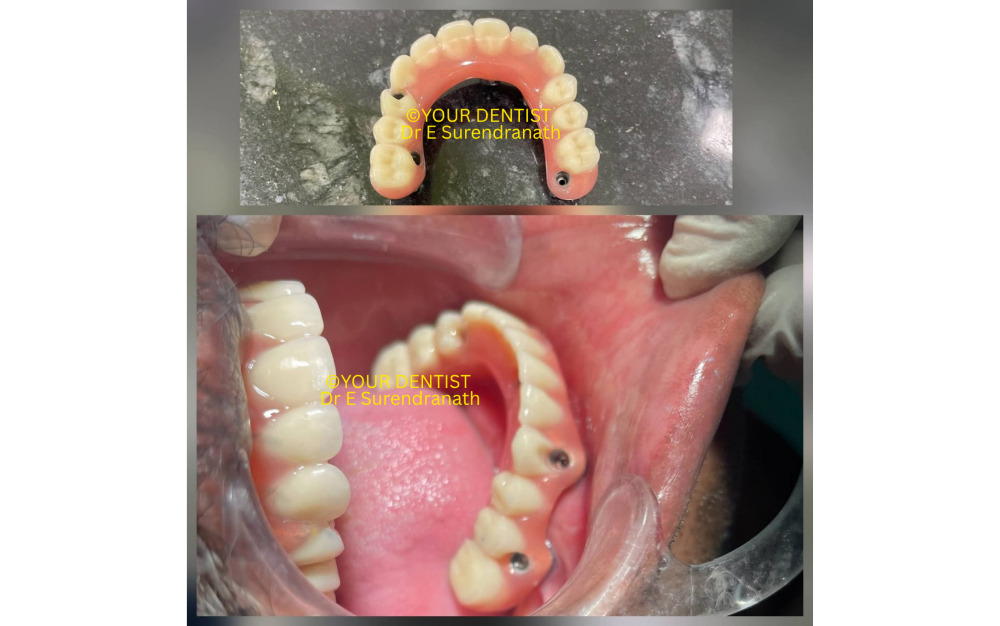

Fig 5

Full arch dental implant prosthesis intraoral view

In immediate loading cases, the choice of prosthesis is just as important as the implant placement itself. A screw-retained acrylic hybrid prosthesis is often a very practical and biologically favorable option during the immediate phase, especially in advanced full-arch cases involving zygomatic implants.

One of the main reasons is weight. In a freshly placed implant case, particularly in the upper jaw with zygomatic support, it is wise to keep the prosthesis relatively light during the initial healing and osseointegration period. Acrylic hybrids are lighter than zirconia or other heavier definitive materials, which helps reduce unnecessary functional load on the implants during the early phase.

Another major advantage is shock absorption. Acrylic teeth and acrylic base tend to absorb and distribute functional forces in a slightly more forgiving way compared to very rigid materials. In immediate loading situations, this can be beneficial because the prosthesis is being delivered when the implants are stable enough for loading, but still biologically in the healing phase.

Screw retention also offers an important clinical advantage. The prosthesis can be retrieved easily whenever needed for hygiene maintenance, soft tissue evaluation, occlusal adjustment, or prosthetic modification. In full-arch immediate loading cases, retrievability is extremely valuable because minor adjustments are often necessary as the tissues heal and the patient adapts to the new bite and function.

From a biomechanical point of view, a screw-retained acrylic hybrid prosthesis acts as an efficient immediate provisional or early fixed restoration because it splints the implants together while keeping the restorative design practical, repairable, and relatively lightweight. In complex cases with severe maxillary atrophy, zygomatic implants, and immediate function, these advantages become even more relevant.

That is why, in many immediate loading full-arch cases, a screw-retained acrylic hybrid denture is often the preferred restorative option during the initial phase before considering a more definitive long-term prosthesis.